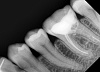

Первое в мире стоматологическое применение Carbon Nano Tube Technology. EzRay Air благодаря инновационной технологии CNT, демонстрирует невероятную легкость, безопасность и стабильную резкость изображений, необходимую для работы с портативным рентгеновским аппаратом.

Автоматическое позиционирование делает процесс подготовки простым. Существуют настройки экспозиции по умолчанию для угла съемки каждого зуба. Оператору необходимо только сопоставить референс-линию с окклюзионной или франкфуртской плоскостью и поднести тубус к месту планируемой съемки, так как угол и зуб будут обнаружены автоматически . Время экспозиции будет установлено автоматически.

EzRay Air нет необходимости запоминать и нажимать множество кнопок для каждой настройки. «Умный» дисплей, имеющий все настройки на одной панели, упрощает работу и сокращает время подготовки к съемке. Встроенный гироскоп контролирует угол наклона тубуса для соблюдения правильного угла съемки и установки времени экспозиции.